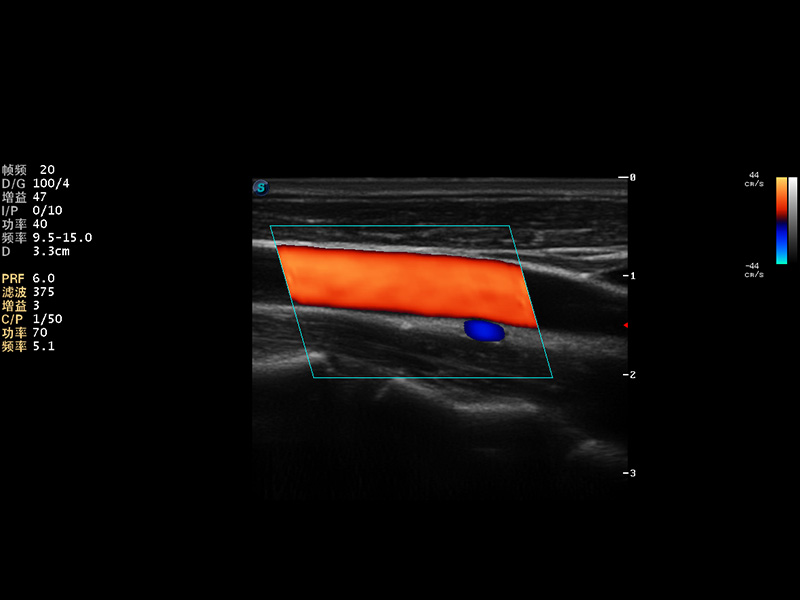

S9便携式彩色多普勒超声诊断仪是狗万官方网站研发的高端便携彩超设备,外观设计新颖、产品性能卓越。S9在便携超声领域采用了突破传统的触摸屏交互设计,并以先进的软件硬件技术和设计理念,为您带来清晰的图像质量、稳定的工作性能和便捷的操作体验。

AutoC智能血流追踪